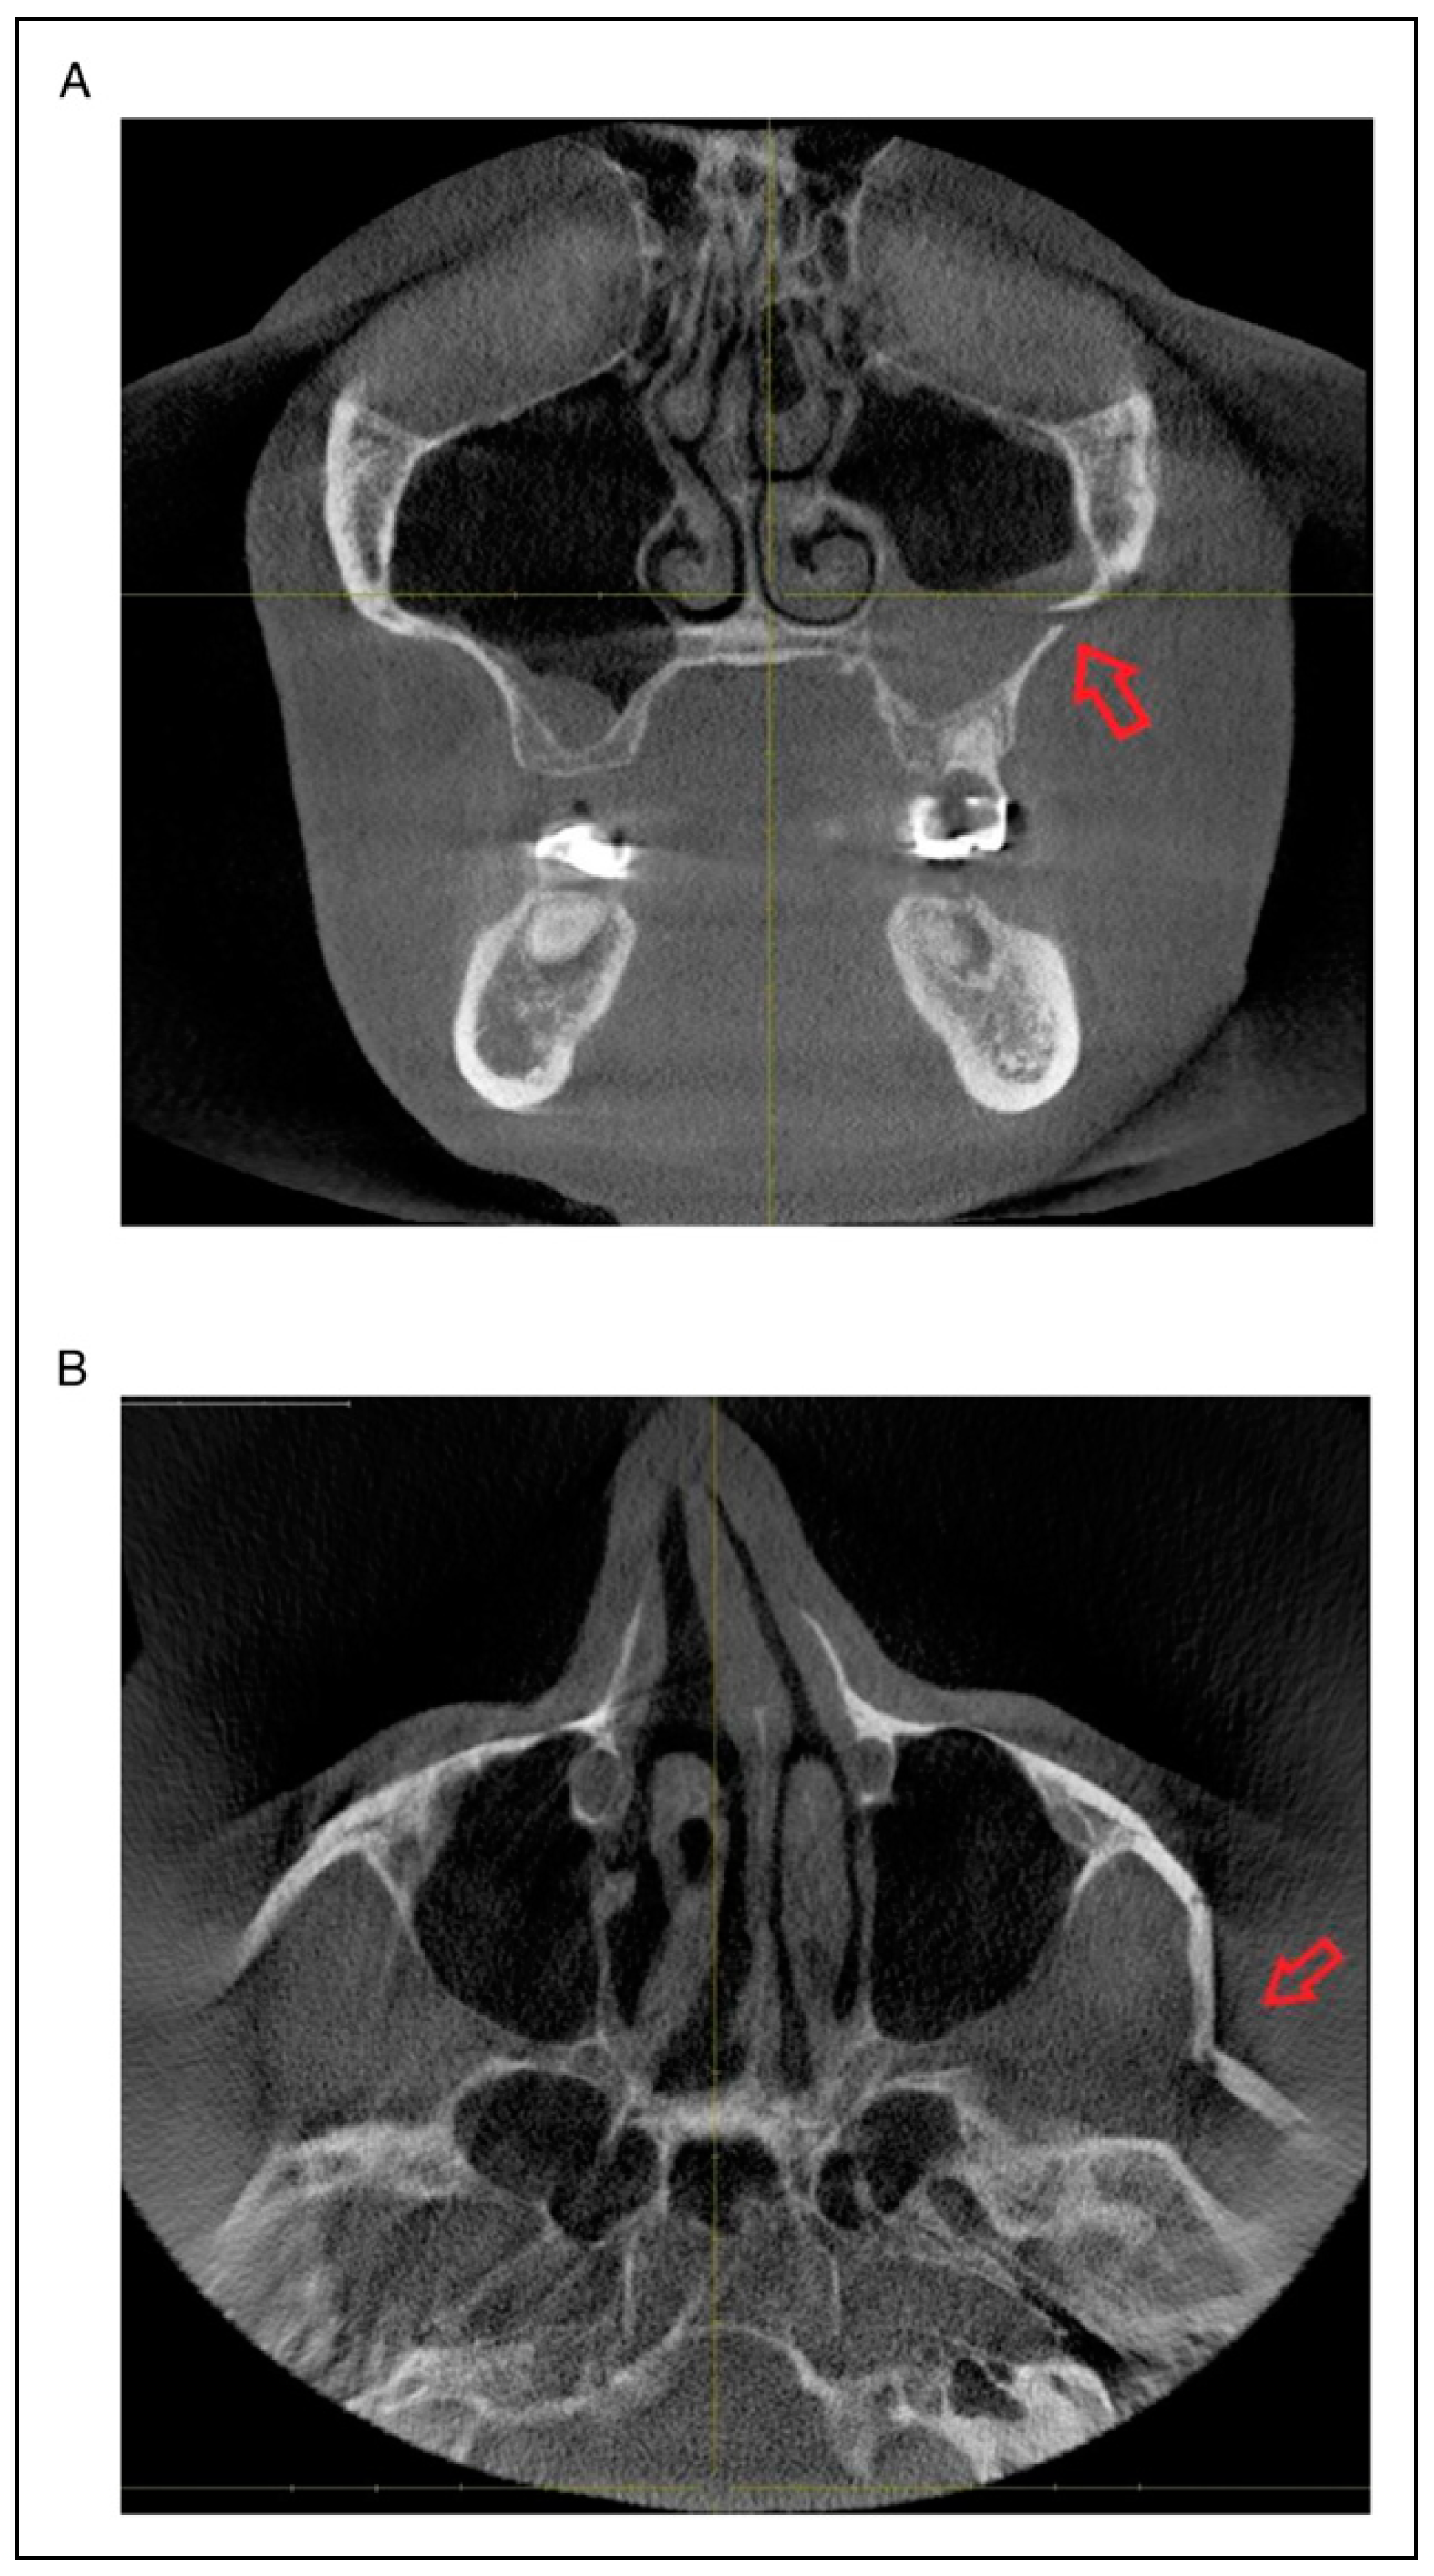

Fracture Prevalence of Maxillary Sinus Wall and Paranasal Buttress as Concomitance to the ZMO

- Radiologic involvement of maxillary sinus wall and paranasal buttress fractures.